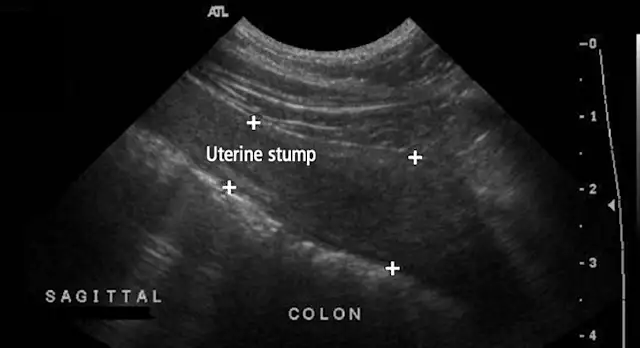

On abdominal ultrasonography, a 15 × 18–mm cystic mass was noted caudolateral to the right kidney (Figure 1C). A second mass (Figure 1D) located dorsal to the urinary bladder and measuring 4.39 × 2.72 cm high (sagittal view) was filled with flocculent fluid. Escherichia coli organisms were isolated on aerobic culture of the vagina.

The perinephric mass and the uterine stump were removed via laparotomy (Figures 1E, 1F, and 1G). Histopathology identified a luteoma originating from a right ovarian remnant as well as uterine stump pyometra with endometrial progesterone influence.